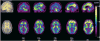

A central issue in cognitive neuroscience of aging research is pinpointing precise neural mechanisms that determine cognitive outcome in late adulthood as well as identifying early markers of less successful cognitive aging. One promising biomarker is beta amyloid (Abeta) deposition. Several new radiotracers have been developed that bind to fibrillar Abeta providing sensitive estimates of amyloid deposition in various brain regions. Abeta imaging has been primarily used to study patients with Alzheimer's Disease (AD) and individuals with Mild Cognitive Impairment (MCI); however, there is now building data on Abeta deposition in healthy controls that suggest at least 20% and perhaps as much as a third of healthy older adults show significant deposition. Considerable evidence suggests amyloid deposition precedes declines in cognition and may be the initiator in a cascade of events that indirectly leads to age-related cognitive decline. We review studies of Abeta deposition imaging in AD, MCI, and normal adults, its cognitive consequences, and the role of genetic risk and cognitive reserve.